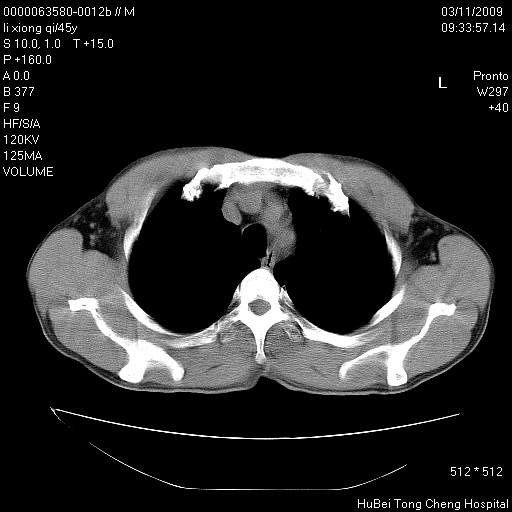

患者 男,45岁。胸痛,咳嗽伴痰中带血1月余。

临床诊断:肺结核?

胸部ct轴位平扫(层厚10mm,螺距1.5,重建间隔10mm),图像如下: